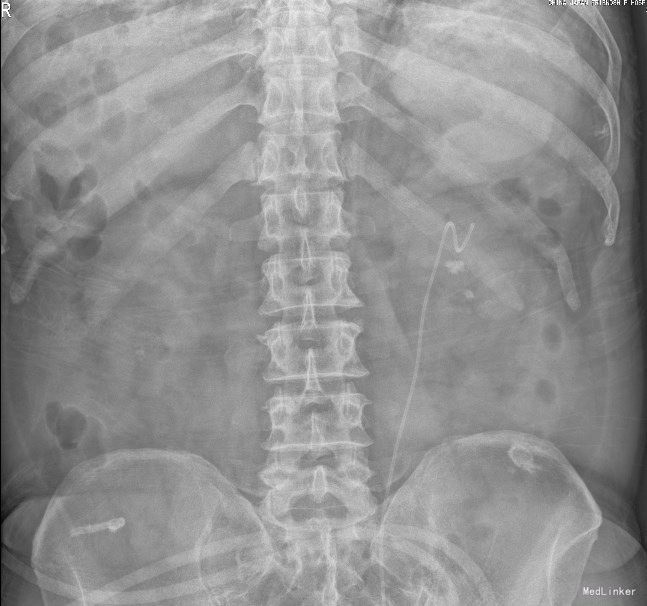

患者男,69岁,主因左侧腰部反复疼痛22年,加重一周。以1.左输尿管结石 2.双肾结石 3.胆囊结石 收入院。患者诉22年前无明显诱因出现右侧腰部疼痛,为钝痛;当地医院诊断为肾结石,予排石散等药物保守治疗,症状缓解;直至2006年患者又突发左侧腰痛,为钝痛,偶伴活动性肉眼血尿,无畏寒发热等症状;曾在北大医院接受体外冲击波碎石术,术后患者症状好转后出院;2015年10月23日我院CT提示:左肾及输尿管上段结石,左肾盂及输尿管上段积水扩张;右肾结石,胆囊结石;门诊以肾输尿管结石收住入院

肾输尿管结石 输尿管镜左输尿管结石碎石术

碎石干净,腹部平片证实